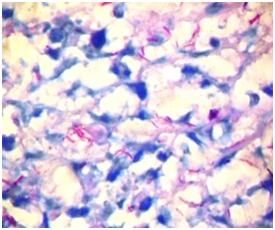

Peritoneal cavity lavage, intestinal resection and Ileostomy were performed. A sample of intestinal tissue was sent for smear microscopy and culture which identified Mycobacterium tuberculosis complex (MTC). The immunocromatography, also detected the MTC and was sensitive to all the first-line anti-TB drugs. The pathology results concluded chronic granulomatous inflammation of tuberculous aetiology with Ziehl Neelsen positive results (Figures 2-4). During her evolution hepatosplenomegaly, ascites and bilateral pleural effusions were also evident. She had also a positive acid-fast bacilli smear microscopy result in stool, tracheal secretion and gastric juice.The patient had a negative purified protein derivative (PPD) skin test. The patient received anti-tuberculous treatment for 12months (two months of rifampicin, isoniazid, pyrazinamide, ethambutol and next 10months of rifampicin and isoniazid) with favorable evolution.

Figure 4 Mycobacterium Tuberculosis Ziehl Neelsen (100x magnification).

The reported incidence of perforation in adults and children varies from 0 to 11% and is very rare in children, however due to the presentation of the disease with nonspecific clinical manifestations, the diagnosis is usually delayed and therefore allows the development of complications and increase of mortality.19 In view of the diagnostic suspicion of intestinal tuberculosis in the patient, a sample of intestinal tissue was sent for staining with Ziehl Neelsen and Culture that showed the bacillus, Mycobacterium tuberculosis. In the treatment of all patients with abdominal tuberculosis, a standard complete course of antituberculosis therapy should be administered. There is still a debate over the duration of treatment. Treatment has been reported to be successful when administered for 12-18months but other authors have reported that a duration of 6months is sufficient. Our patient received antituberculous therapy for 1year with favorable evolution.20,21